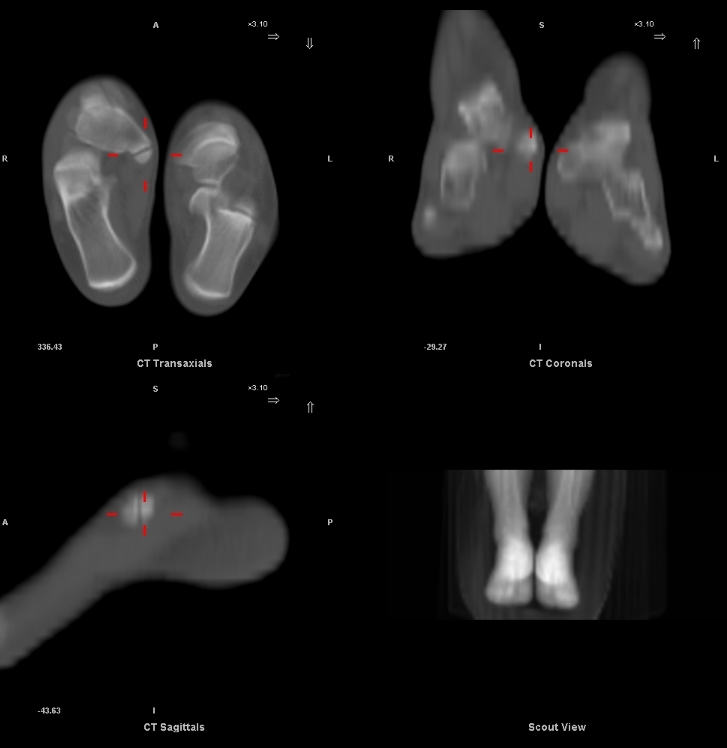

Sur les coupes TDM de repérage: ostéo-condensation sous chondrale des berges en rapport avec des remaniements dégénératifs.